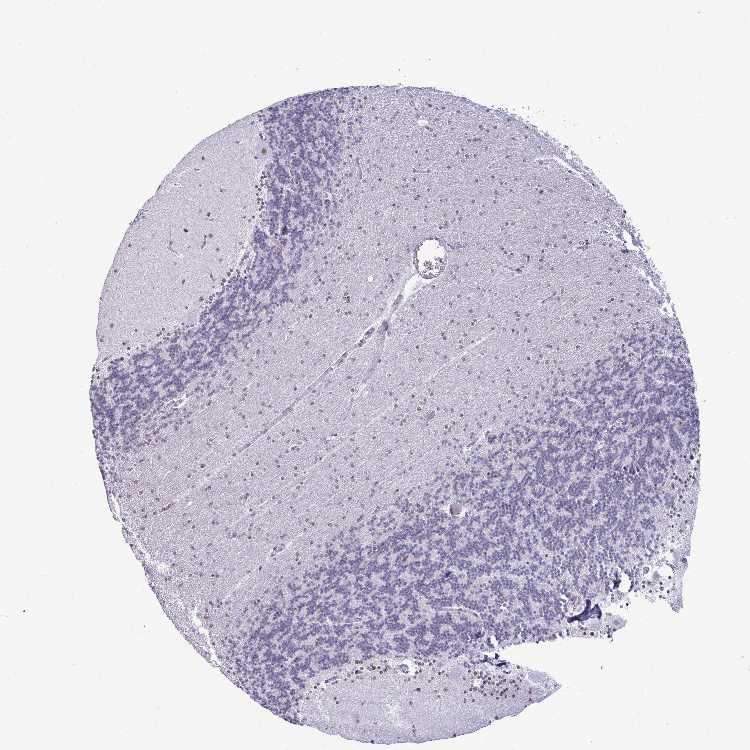

BRAIN CEREBELLUM Show tissue menu

CEREBELLUM - Expression summary

CEREBELLUM - Antibody stainingi

Antibody staining in the annotated cell types in the current human tissue is reported as not detected, low, medium, or high, based on conventional immunohistochemistry profiling in selected tissues. This score is based on the combination of the staining intensity and fraction of stained cells.

Each image is clickable and will lead to virtual microscopy that enables deeper exploration of all samples and also displays staining intensity scores, fraction scores and subcellular localization as well as patient and tissue information for each sample.

Antibody HPA060760

Purkinje cells High

Cells in granular layer Not detected

Cells in molecular layer Medium